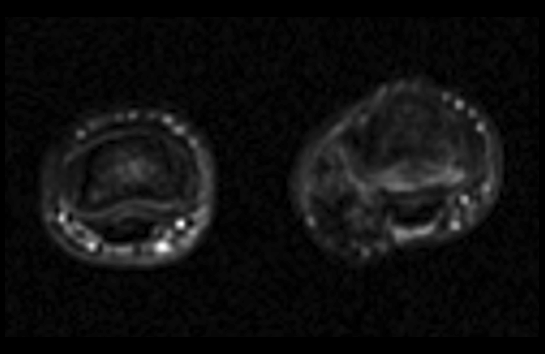

Se solicitan pruebas de imagen: RX, ECO, RM.

2. ¿Como describirías los hallazgos en RM?

- A. Lesión dependiente de la polea A2.

- B. Tumoración de partes blandas relacionada con la vaina tendinosa.

- C. Sinovitis dependiente del espacio interfalángico.

- D. Tumoración dependiente de la falange media con componente de partes blandas.

- E. Tumoración de aspecto vascular.